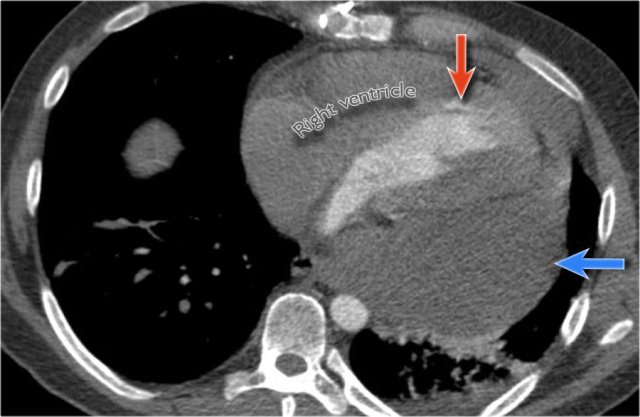

Postoperative Pericardial Hemorrhage

In patients with recent cardiac surgery, a sudden change in heart size on chest X-ray should raise suspicion for pericardial bleeding, which may be life-threatening.

Case Example 2:

• A postoperative patient showed a change in the cardiac silhouette.

Case Example 2 - CT imaging

• CT imaging revealed a large posterior pericardial effusion compressing the left ventricle (blue arrow: effusion; red arrow: compressed, contrast-filled left ventricle).

• Surgical exploration confirmed a large posterior pericardial hematoma.

Note

: Minimal anterior fluid on ultrasound may underestimate the true volume if the effusion is loculated posteriorly, highlighting the value of CT in postoperative cases.